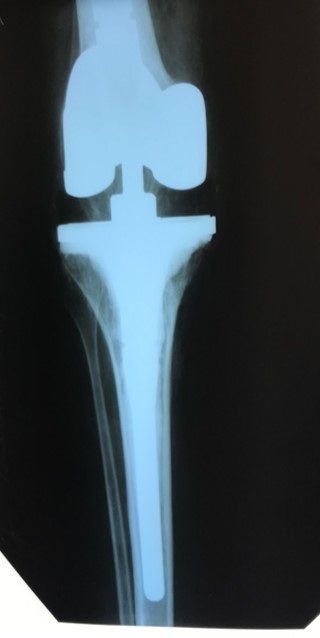

Приклад 4. Хвора Г. 72 років. Діагноз: Деформівний IV ст. гонартроз, стан після ТЕП КС (2010р.). Гемартроз в післяопераційному періоді, хронічний синовііт.Септична нестабільність компонентів ендопротеза  колінного суглоба на протязі року. Виявлений дефект виростків стегнової кістки  тип Т3, F 3 за класифікацією АОRI [G.A. Engh, C.H. Rorabeck, 1997]. Хворій виконано  двоєтапне ревізійне ендопротезування: видалення компонентів ендопротезу іплантовано спейсер з антибіотиком. Піcля санаціїї виконано другий єтап певізії, імплантовано ревізійний ендопротез колінного суглоба.